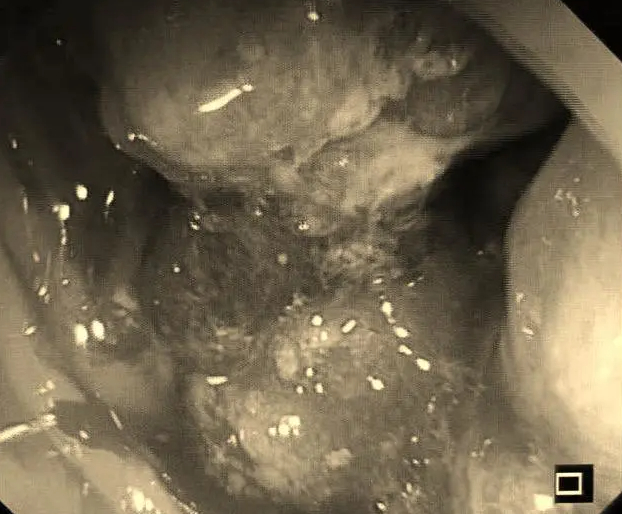

距肛门10-12cm处,一个巨大环周性占位!直肠癌,而且应该是晚期!

巨大占位性病变

通过肠镜能直视结直肠内部,观察肿块的形态,上下缘及距肛门缘的距离,同时可取病理送检,确定肿块性质及分化程度。